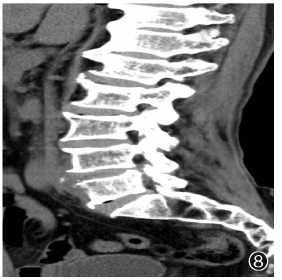

| 图8 病例6,男性,81岁。患者于2021年6月3日在陕西省结核病防治院摄腰椎CT(矢状面),显示腰1~骶1椎体前缘骨质增生变尖,腰5椎体前缘骨质轻度破坏,椎前可见低密度软组织影 |